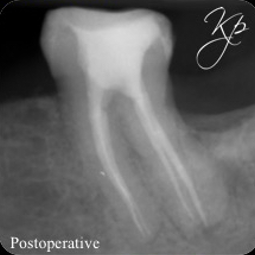

A detailed clinical and radiographic examination (as detailed above) are important to identify the presence of radix entomolaris or radix paramolaris (Figure 6).

The access cavity will need extending in the direction of the extra canal (RE: disto-lingual or RP: mesio-buccal). A blunt-ended bur (such as an Endo-Z bur) is very useful to enlarge the access as required. Ultrasonics also provide a controlled and conservative way of refining the shape of the access cavity to allow straight line access.

The coronal part of the radix canal is often significantly curved. It is important to spend time coronally flaring to prevent creating a ledge here. I find the nickel titanium rotary orifice openers particularly useful for this (such as XA or SX by Dentsply Sirona).

Following this, the clinician can create a manual glide path using small hand files (up to a size 10).

Similarly, larger stainless steel hand files are stiffer and can lead to canal transportation. I recommend using flexible nickel titanium instruments to shape after the initial glide path is formed.

The canal may need tackling in two or three sections if the instruments struggle to progress to length. Be careful not to push the files. This can result in ledge formation or file fracture.